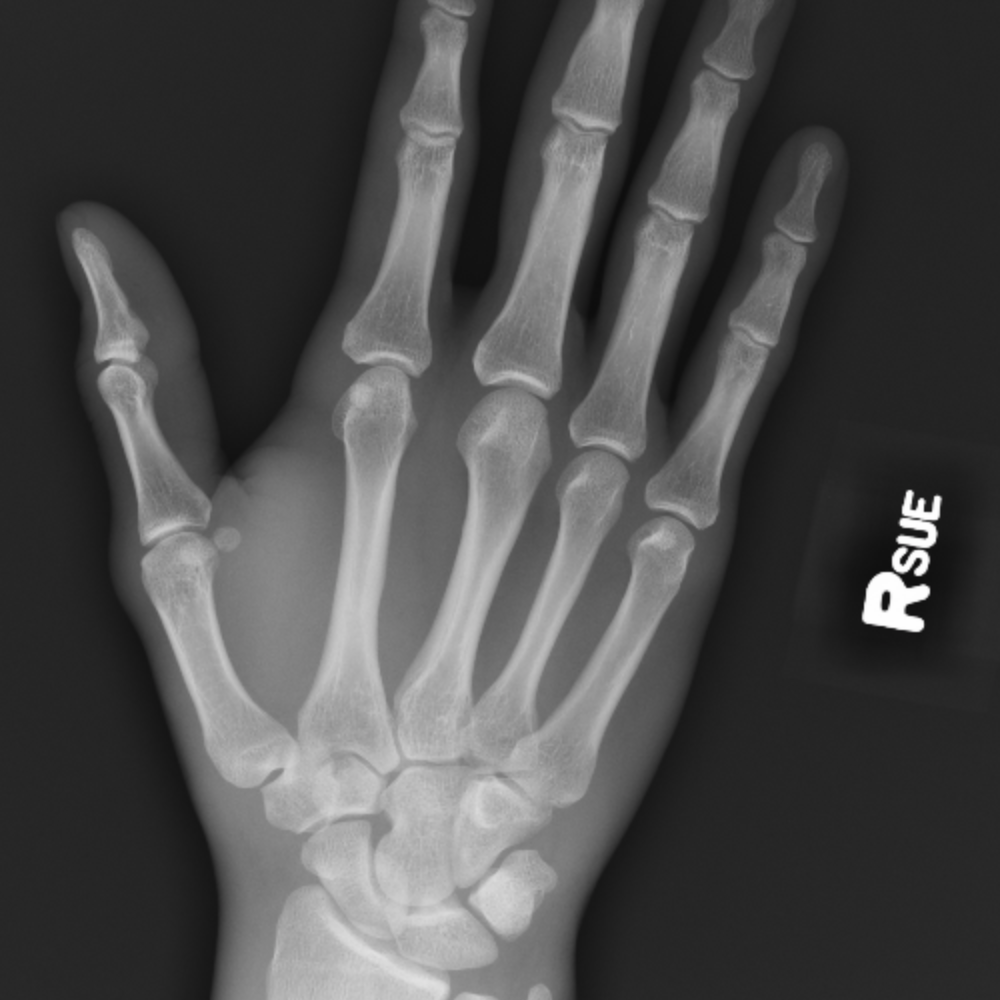

During the first decade of life, enchondral ossification of the scaphoid begins with the appearance of an ossific nucleus. A scaphoid fracture is a break of the scaphoid bone in the wrist.

This is a surgical video intended for patient educational purposes. Distal radius fractures, scaphoid fractures, metacarpal and phalangeal fractures, nailbed injuries, and amputations are among the pediatric hand and wrist injuries most often seen by ort … It appears justified to limit radiographic. Fractures of the scaphoid may not be evident on the initial radiographic examination. Scaphoid fractures are the most common type of carpal injuries that occur in children and mri can aid in the diagnosis of a scaphoid injury in pediatric patients with incomplete ossifi cation of the. Carpal scaphoid fracture, carpal navicular fracture1. Superficial palmar branch of radial a volarly & dorsal capsal branch of radial a. Scaphoid fractures are quite common, but they can be difficult to detect. Scaphoid fracture is a common injury encountered in family medicine. Nonunion may occur as a. Contemporary injury patterns and factors letourneau p.r., zlotolow d.a. To avoid missing this diagnosis, a high index of suspicion and a thorough history and physical examination are necessary. During the first decade of life, enchondral ossification of the scaphoid begins with the appearance of an ossific nucleus. Tuberosity, transverse documented surgical methods for managing scaphoid fracture in the pediatric patient. International journal of radiology 2018; Treatment may require a prolonged period of cast immobilization, percutaneous surgical fixation. Once diagnosed, most pediatric scaphoid fractures can be successfully treated with cast immobilization.